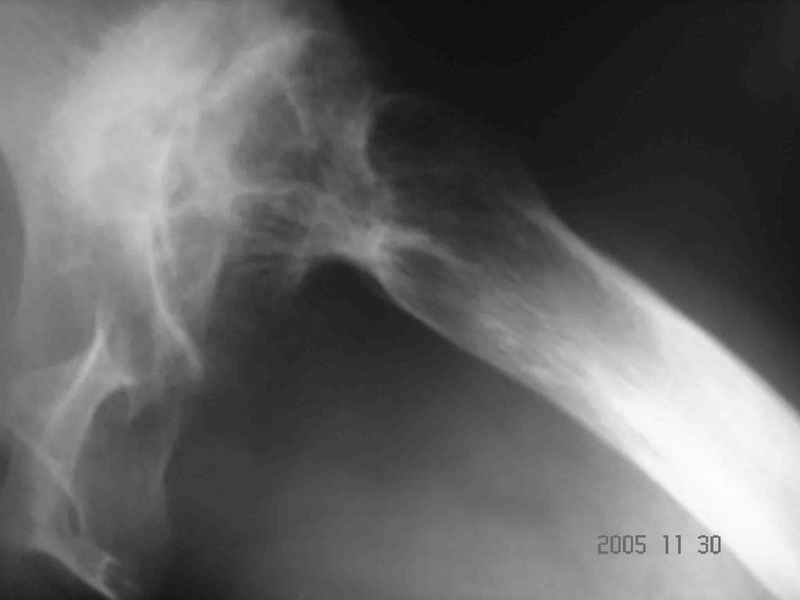

Аксиальный Р-снимок

Шишков Алексей (ГКБ№13 г. Уфа)